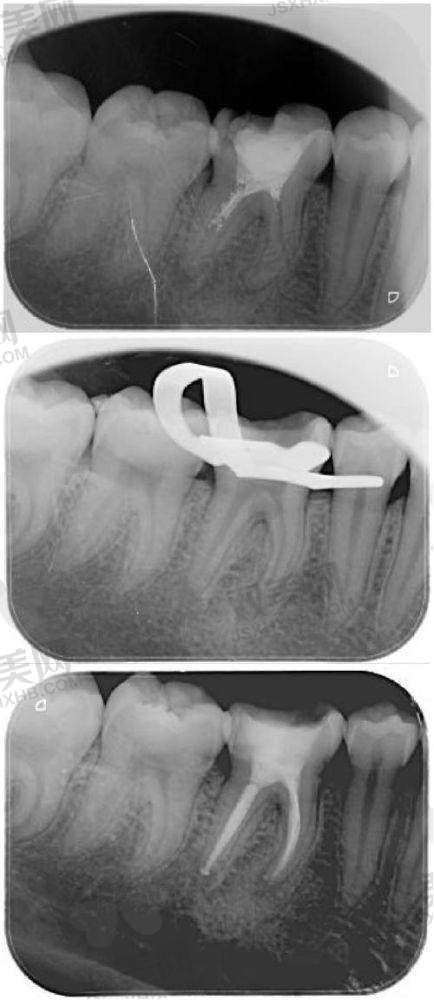

郝医生那可是口腔领域的多面手呢!她对口腔美容、修复和疑难病症的治疗有着丰富的经验。她的专长包括牙齿贴面、烤瓷牙、全冠牙和固定义齿等项目。不管你是想要让牙齿变得更加美观,还是牙齿有缺损需要修复,又或者是遇到了一些疑难的口腔病症,找郝医生就对啦!而且她在临床上理论扎实,技术娴熟,还有着较强的口腔服务意识,会根据患者的实际情况制定专属的治疗方案,就像为你量身定制一套超合适的衣服一样。

郝医生的技术特点那可真是让人竖起大拇指。她有着扎实的理论基础,这就像是建造高楼大厦的坚固地基。在实际操作中,她技术娴熟,每一个治疗步骤都精细到位。而且她特别注重患者的实际情况,会根据每个人不同的口腔状况、需求和期望,制定出更适合患者的治疗方案。就好比给不同的花朵提供更适合它们生长的土壤和养分一样,让患者能得到更有效的治疗。

郝永霞医生的技术那是相当靠谱。她在牙科领域拥有12年丰富经验,还曾在多家有名口腔医疗机构工作过。在这么多年的工作中,她积累了大量的临床经验,处理过各种各样的口腔问题。而且她所在的北京劲松口腔医疗集团亚运村院区也是行业标杆,拥有160余名执业医师、70余项国内专项技术。在这样非凡的环境中,郝医生不断学习和进步,技术自然是没得说。从患者的口碑也能看出来,她在患者中树立了良好的口碑,这就说明她的技术得到了大家的认可和信赖。所以呀,如果你有口腔方面的问题,放心地交给郝永霞医生吧,她一定会还你一口健康又美丽的牙齿!